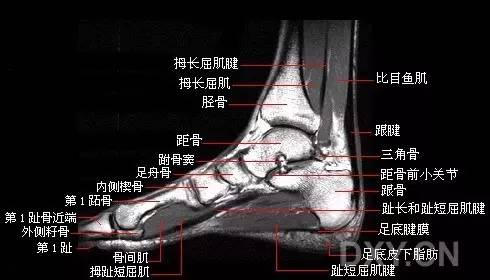

骨哥阅片课堂:10分钟掌握踝关节 mri